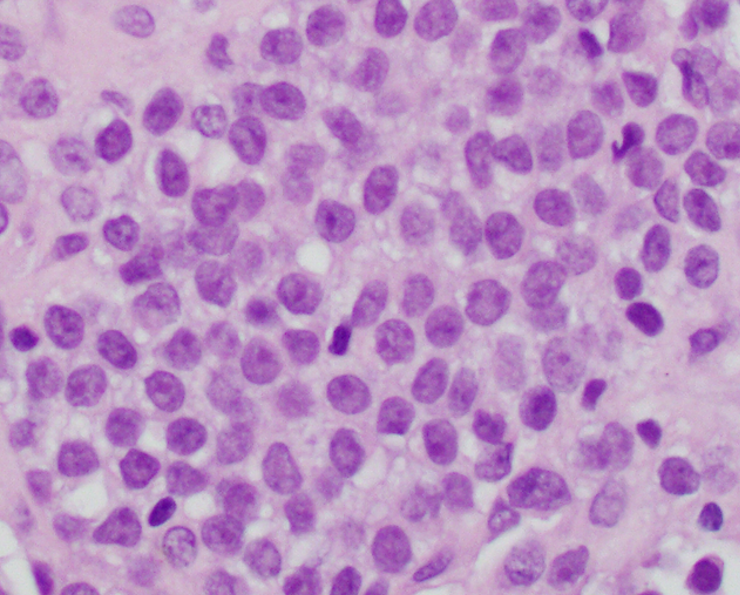

- Atypical Ewing sarcoma (Virchows Arch 2011;458:281)

- Nuclear enlargement

- Irregular nuclear contours

- Vesicular or coarse chromatin

- Prominent nucleoli

Microscopic (histologic) images